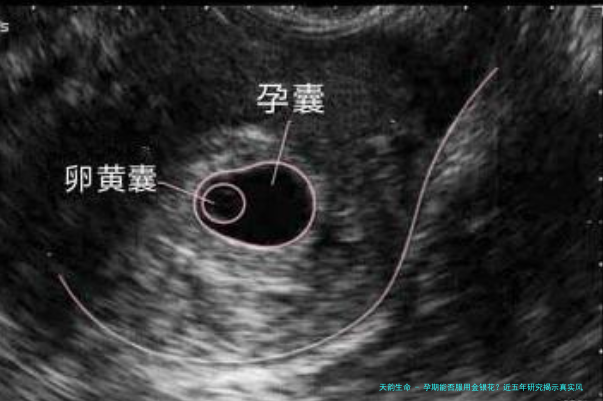

32岁的晓雯怀孕6周时,因咽喉肿痛连续10天每天喝金银花茶。产检时NT值异常让她吓坏了,结果羊水穿刺显示染色体正常,宝宝出生后也很健康。医生分析可能是心理压力导致的假阳性。这个案例告诉我们:与其纠结某味中药,不如保持整体健康的生活方式。